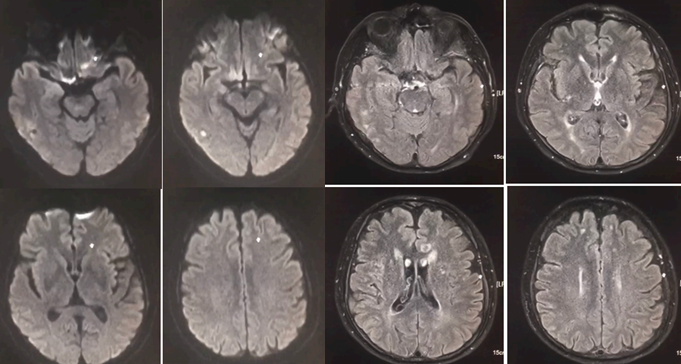

患者59岁女性,头痛恶心呕吐2天。

答案:可逆性后部脑病综合征(PRES)。PRES本质上是一种可逆性的血管源性水肿,伴急性神经系统症状,如癫痫发作,脑病,头痛,视觉障碍等,常见原因为高血压、肾衰竭、使用细胞毒性药物、自身免疫性疾病、子痫前期或子痫。PRES常由急剧的血压波动或细胞因子对血管壁的直接作用致内皮损伤,引起血脑屏障的破坏,继而引起脑水肿。本病通常是可逆性,包括影像学表现和临床症状,预后多数较好。复查头MRI如下: